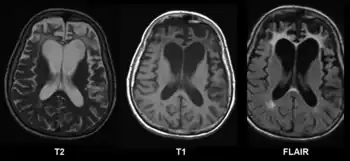

Difference from hydrocephalus

Cerebral atrophy can be hard to distinguish from hydrocephalus because both cerebral atrophy and hydrocephalus involve an increase in cerebrospinal fluid (CSF) volume. In cerebral atrophy, this increase in CSF volume comes as a result of the decrease in cortical volume. In hydrocephalus, the increase in volume happens due to the CSF itself.[20]

Typical imaging findings in normal pressure hydrocephalus versus brain atrophy.[21]

Normal pressure hydrocephalusBrain atrophy

Preferable projectionCoronal plane at the level of the posterior commissure of the brain.

Modality in this exampleCTMRI

CSF spaces over the convexity near the vertex (red ellipse )Narrowed convexity ("tight convexity") as well as medial cisternsWidened vertex (red arrow) and medial cisterns (green arrow)

Callosal angle (blue V)Acute angleObtuse angle

Most likely cause of leucoaraiosis (periventricular signal alterations, blue arrows ) Transependymal cerebrospinal fluid diapedesis Vascular encephalopathy, in this case suggested by unilateral occurrence